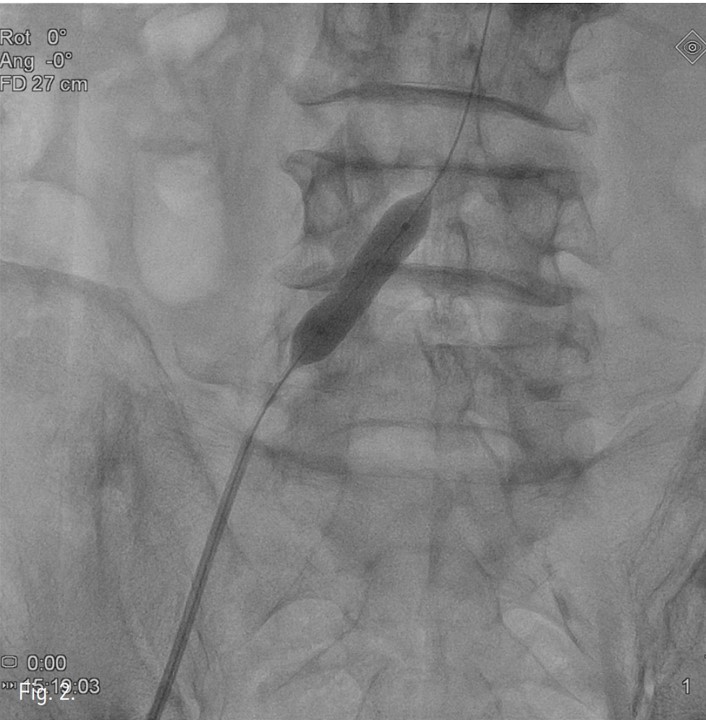

컴퓨터단층촬영 혈관조 영술과 고식적 혈관조영술에서 우측 총장골동맥에 석회화를 동반한 80%정도의 심한 협착이 있고, 좌측 총장골동맥에서 외장골동맥에 석회화를 동반한 완전 폐쇄의 소견이 있다 (Fig. 1A, IB). 우총대퇴동맥의 근위부에 10mm x 29mm Zenesis stent를 설치하였다 (Fig. 2). 0.035 inch guidewire로 좌측 총장골동맥의 기시부 폐쇄부위 통과를 시도하였으나 가성내강에서 진성내강으로 재진입이 되지 않았다 (Fig. 3). 좌측 외장골동맥 진성내강 내에 있는 ‘L-자’ 표시방향의 outback device가 보인다 (Fig. 4A), 좌측 외장골동맥 진성내강 내에 있는 'T-자’ 표시방향의 outback device가 보인다(Fig. 4B). Outback device를 이용하여 동맥내막을 천자후 0.014 inch guidewire를 가성내강 내로 진입시켰지만 좌측 총장골동맥-외장골동맥경 계부위에서 더 이상 진행되지 않았다 (Fig. 4C). 0.014 inch guidewire를 따라서 Davis catheter를 가성내강 내로 진입시키고 (Fig. 5A), 10mm snare를 삽입하여 Simmon catheter내부에 있던 microwire를 전진시켜 snare로 잡아 좌측 sheath로 뽑아내어 (Fig. 5B), 5Fr. Davis catheter를 대동맥 내부로 진입시켰다(Fig. 5C). 양측 총장골동맥 및 좌측 외장골동맥 스텐트 설치후 대동맥장골동맥조영술상에서 양측 장골동맥의 완전한 재개통을 보인다 (Fig. 6).

Fig. 2.

Fig. 2. Balloon expandable stent (10mm x 29mm) was deployed at right common iliac artery.